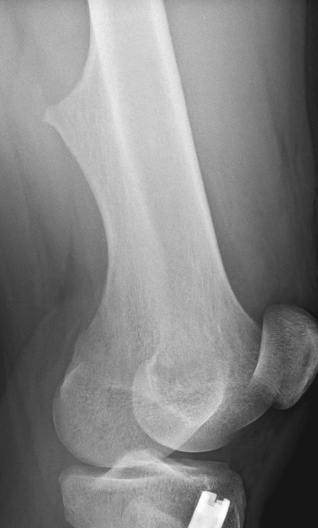

Plain radiographs of the knee are shown.

Along with mild soft tissue swelling in the distal thigh, the radiographs show an eccentric cortical outgrowth from the distal femur, directed away from the joint (A and B). The rod and nail present in the proximal tibia is related to a prior fracture.

The image findings are classic for osteochondroma. This cartilage-capped bony projection may arise from the external surface of any bone of cartilaginous origin. However, osteochondromas most commonly occur in the long bones. Similar to the physeal growth plate, an osteochondroma ceases to grow at puberty; cartilage decreases in thickness and undergoes ossification.